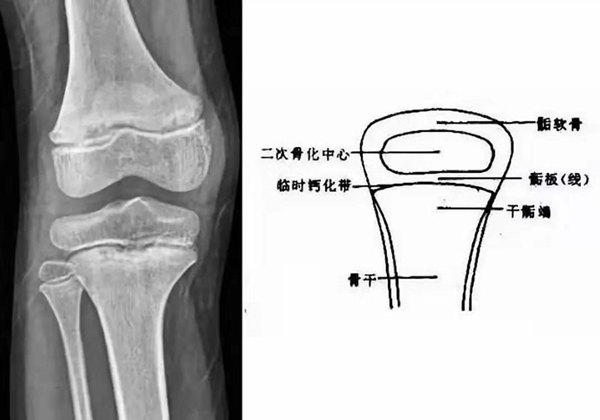

我們都知道,人體的高矮是由骨骼的生長(zhǎng)發(fā)育決定的,特別是下肢長(zhǎng)骨。長(zhǎng)骨呈長(zhǎng)管狀,在長(zhǎng)骨的兩端有一種專(zhuān)管骨骼生長(zhǎng)的骺軟骨,它與干骺端之間有一盤(pán)狀軟骨結(jié)構(gòu)稱(chēng)為骺板(線(xiàn)),在幼兒的X光片上表現(xiàn)為一條較寬的透光帶。 (見(jiàn)下圖)

未成年時(shí)隨著年齡的增加骺軟骨端不斷骨化,骨骼就不斷增長(zhǎng)。當(dāng)骨骺線(xiàn)完全閉合時(shí)骨骼就停止生長(zhǎng),個(gè)子也就不再增長(zhǎng)了。一般骨骺端完全閉合的年齡是18~20歲左右。